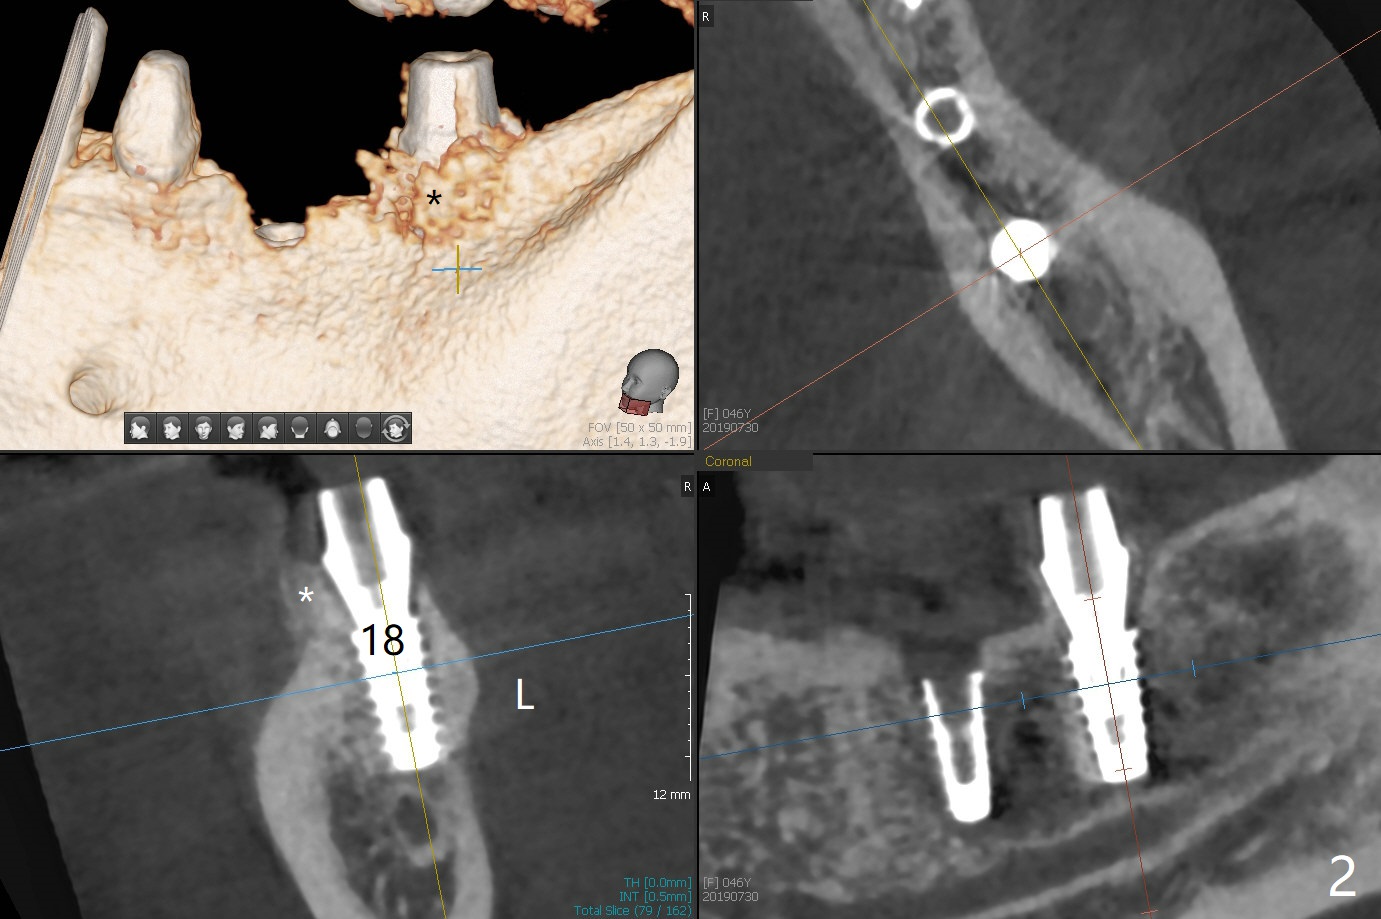

The female woman is afraid of pain. After placement of 4x9 mm FC implant at #19, infiltration anesthesia is not enough for osteotomy at #18. Block anesthesia is added. When a 5x9 mm FC implant is placed in the osteotomy (designed for 5x8.5 mm IS one), it is close to the Inferior Alveolar Canal (Fig.1 red dashed line; Fig.2 (*: bone graft with PRF)). The third contributing factor is the pressure upon the distal end of the distal end guide while osteotomy. A few hours later, the patient reports no paresthesia. The implant placement level and trajectory are normal at #18 and 19 (Fig.3-5). To check pair abutment seating with 30 Ncm torque, PA is taken after removal of healing abutments 4 months postop (Fig.6-8). First the cuff of the abutment is short, subgingival distal of #18 (Fig.6 * (gingiva)). When an abutment with longer cuff is placed, it appears to be close to the distal crestal bone (Fig.7 *). Finally a smaller abutment seams to be appropriate (Fig.8). Retrospectively the larger abutment (6.5x4(4) mm) is incompletely seated initially (Fig.1 with gap).